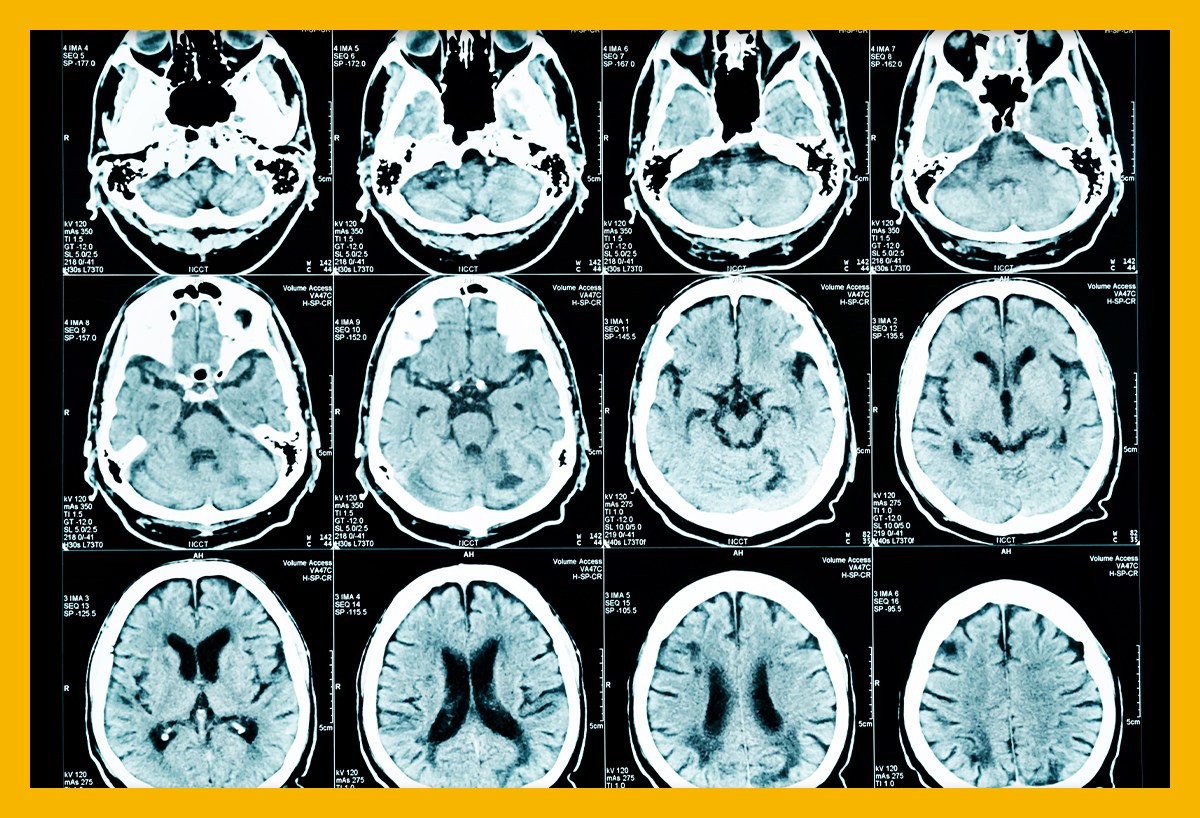

뇌경색 초기증상에 대하므로 살펴볼게요니다. 뇌에도 혈관이 있어서 피가 흐르고 있어요. 뇌에 있는 혈관이 막혀서 뇌의 일부가 손상되는 것을 뇌경색이라고 말해요. 뇌혈관이 막혀 뇌가 손상되면 장애가 발생할수 도 있으므로 뇌 연관 질환은 각별한 주의가 필요해요.

뇌에 제공되는 혈액량이 줄어들게면 뇌가 수습해야 되는 역할들을 제대로 실행해 낼 수 없게 돼요. 뇌혈류가 연속적으로 감소되면 뇌조직에 괴사가 시작되고 괴사된 뇌조직이 회복 불가능한 상태가 되면 뇌경색이라고 진단을합니다. 그러므로 뇌경색 초기증상을 알아두고 방지해억제해하시는게 중요해요.

뇌경색은 병에 걸려 후 얼마나 빨리 치료를 착수하는지에 따라 병의 증세가 결심되기도 합니다. 증상이 발생하면 아주많이 빨리 병원을 가서 초급성기 치료를 받아야합니다. 급성기 치료 후에는 이유가 되는 것에 따라 재발 방지를 위한 치료를 하게 되며 후유증에 대한 재활치료도 가능한 한 빨리 실행하는는게게 좋바람직해요. 증상이 처음 나타난 후 4~5시간이 경과하지 않으신다면 주사 제제를 통한 혈전용해술을 시도해 볼 수 있어요. 그리고 24시간이 경과하지 않았고 대뇌혈관이 막힌 것을 확인했으면 막힌 혈관에 대하여서 스텐트 투여술과 같은 기계적 재개통술을 시도할 수 있습니다.